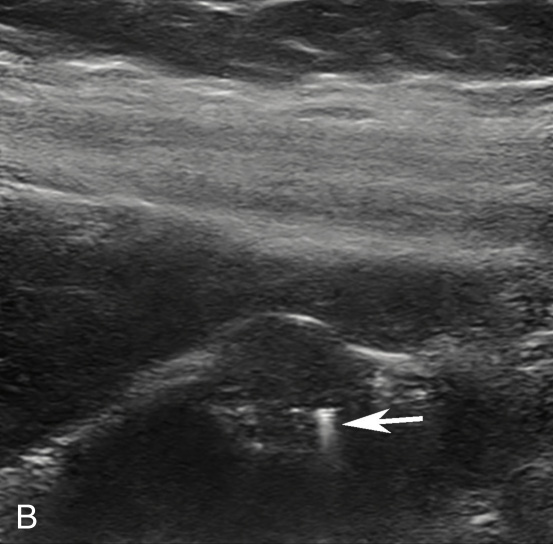

(3)弥漫型胆囊腺肌症:

又称广泛型,胆囊壁呈广泛性增厚(图2-4-3),部分病例胆囊壁上可见多发点状强回声。

图2-4-3 弥漫型胆囊腺肌症常规超声图像

A.胆囊壁呈弥漫性增厚;B.高频超声显示增厚的胆囊壁上可见多发点状强回声;C.CDFI显示“快闪伪像”